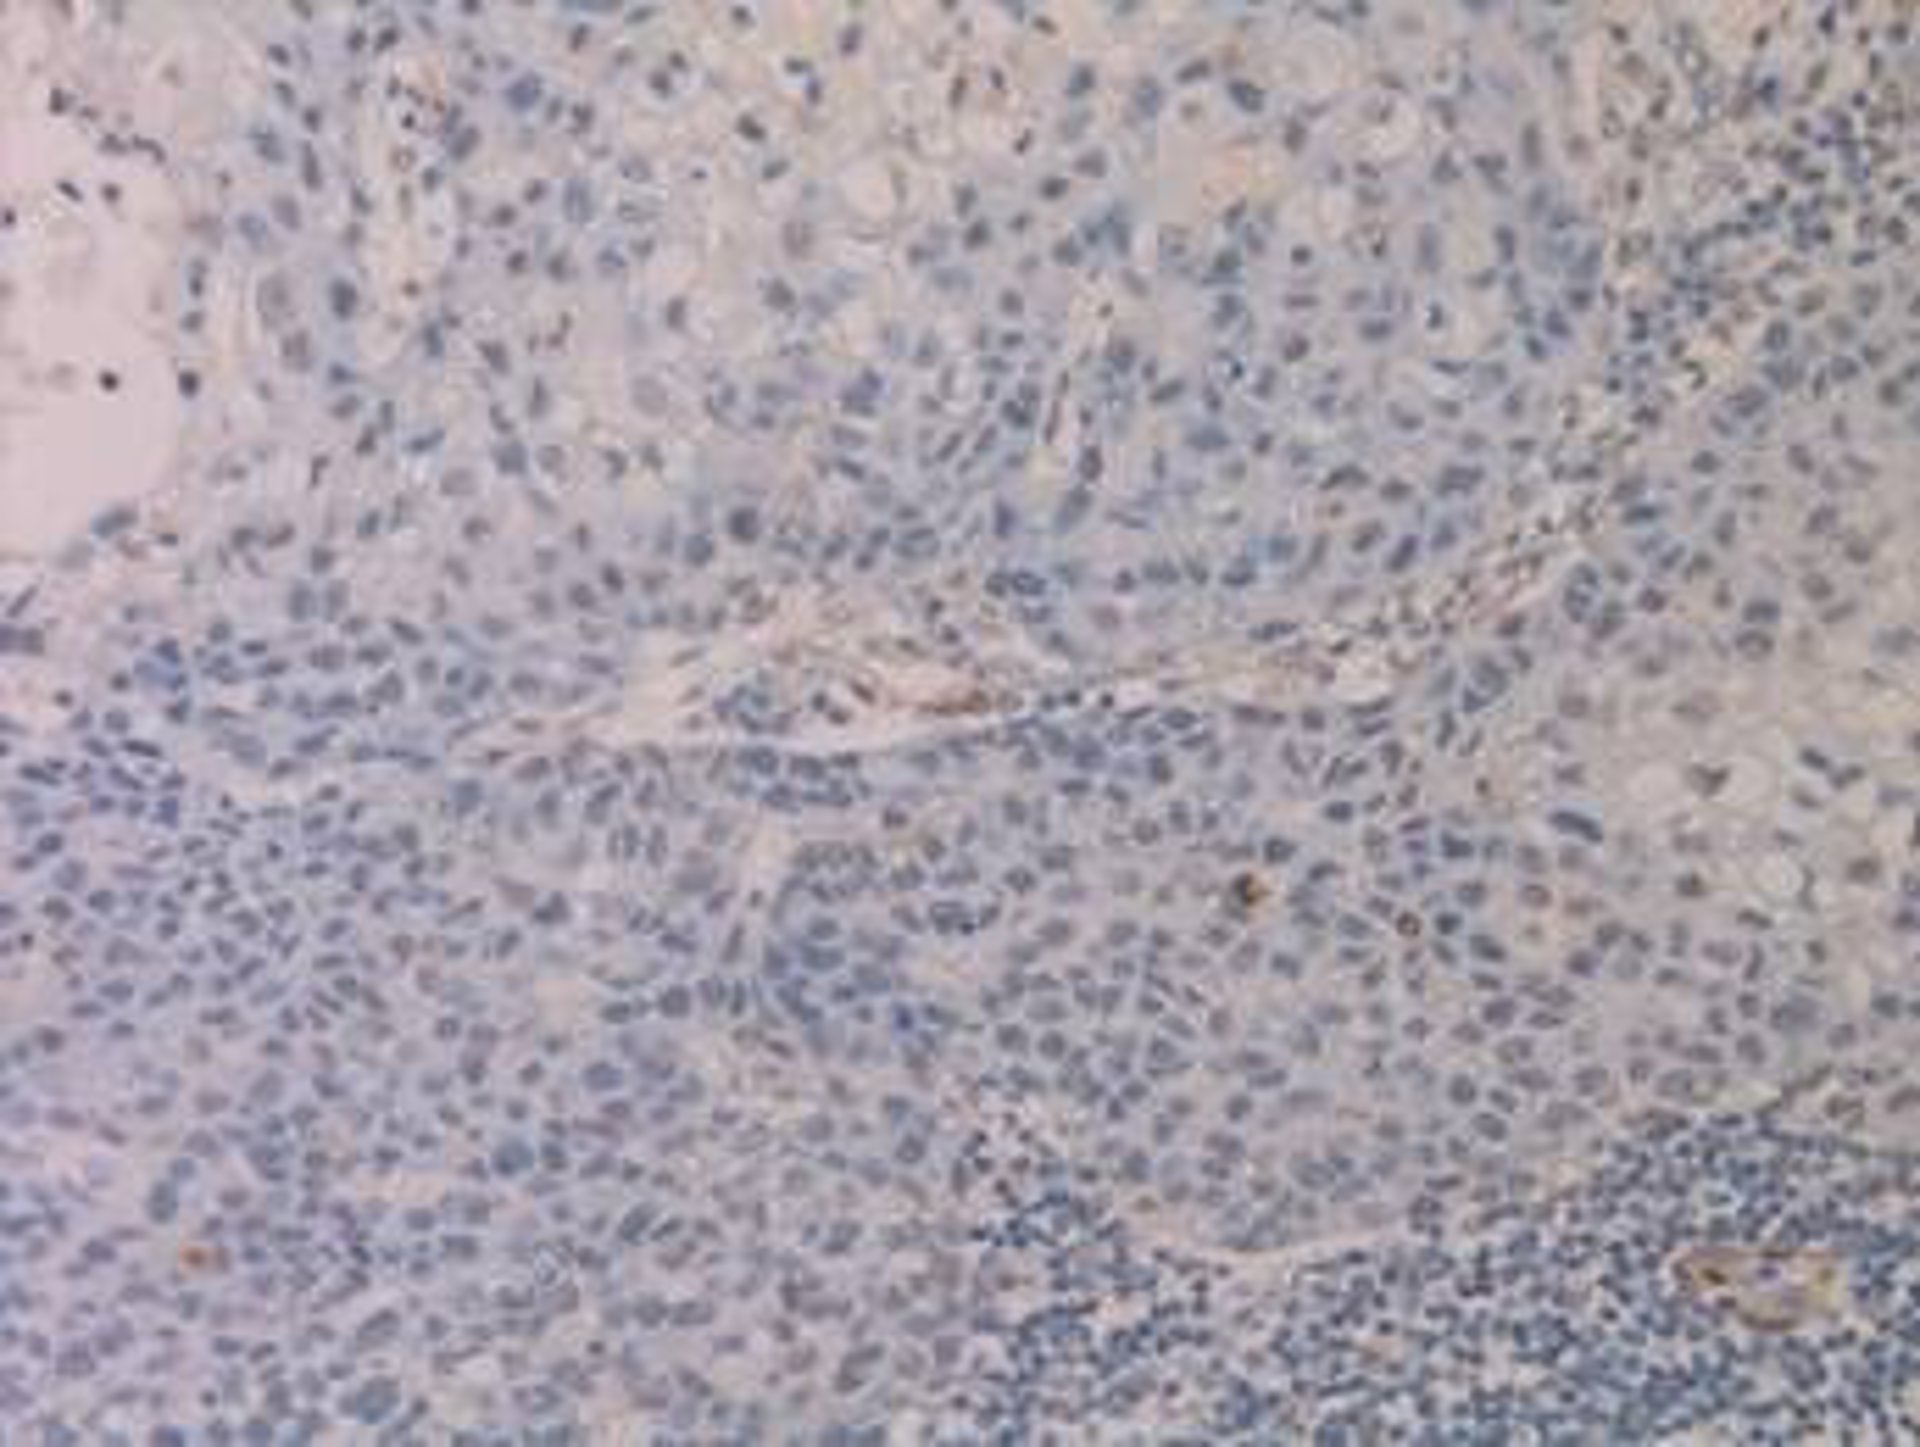

Ganglio Linfático Con Metástasis Que Ha Perdido La Expresión De Una Proteína

La investigación, liderada por el director del programa de Epigenética y Biología del Cáncer del Idibell, Manel Esteller, y que publica la revista 'The Journal of Pathology', se centra en los pacientes con melanoma y tumores de cabeza y cuello, en los que se ha demostrado que la proteína Caderina-11 pierde actividad cuando el tumor se instala en los ganglios linfáticos.